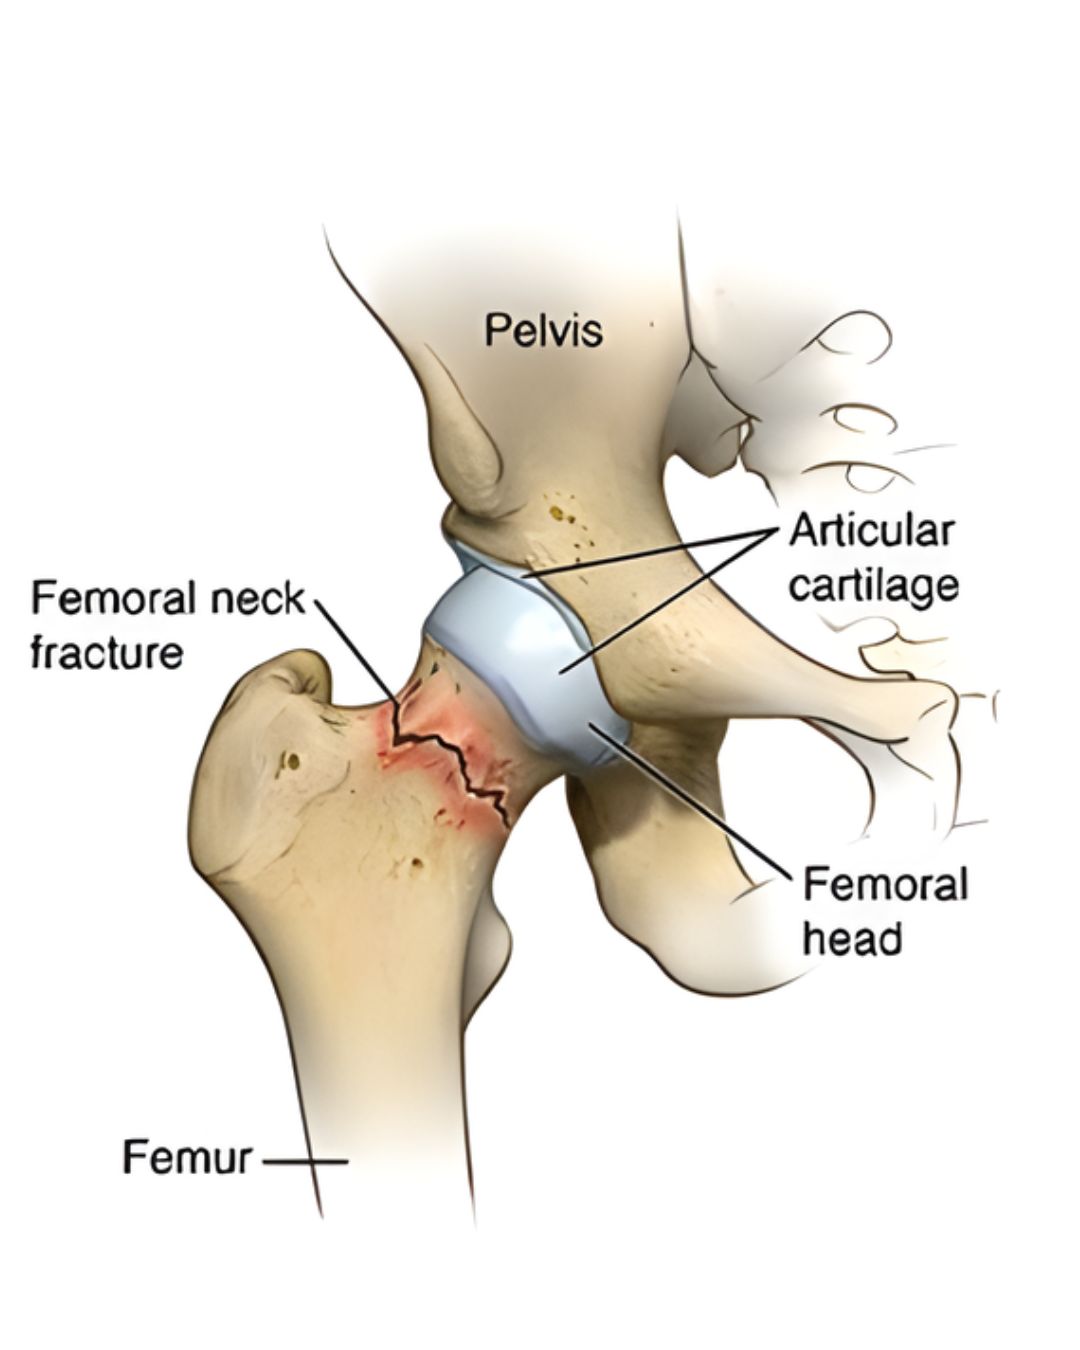

Hip fracture (especially in elderly patients)